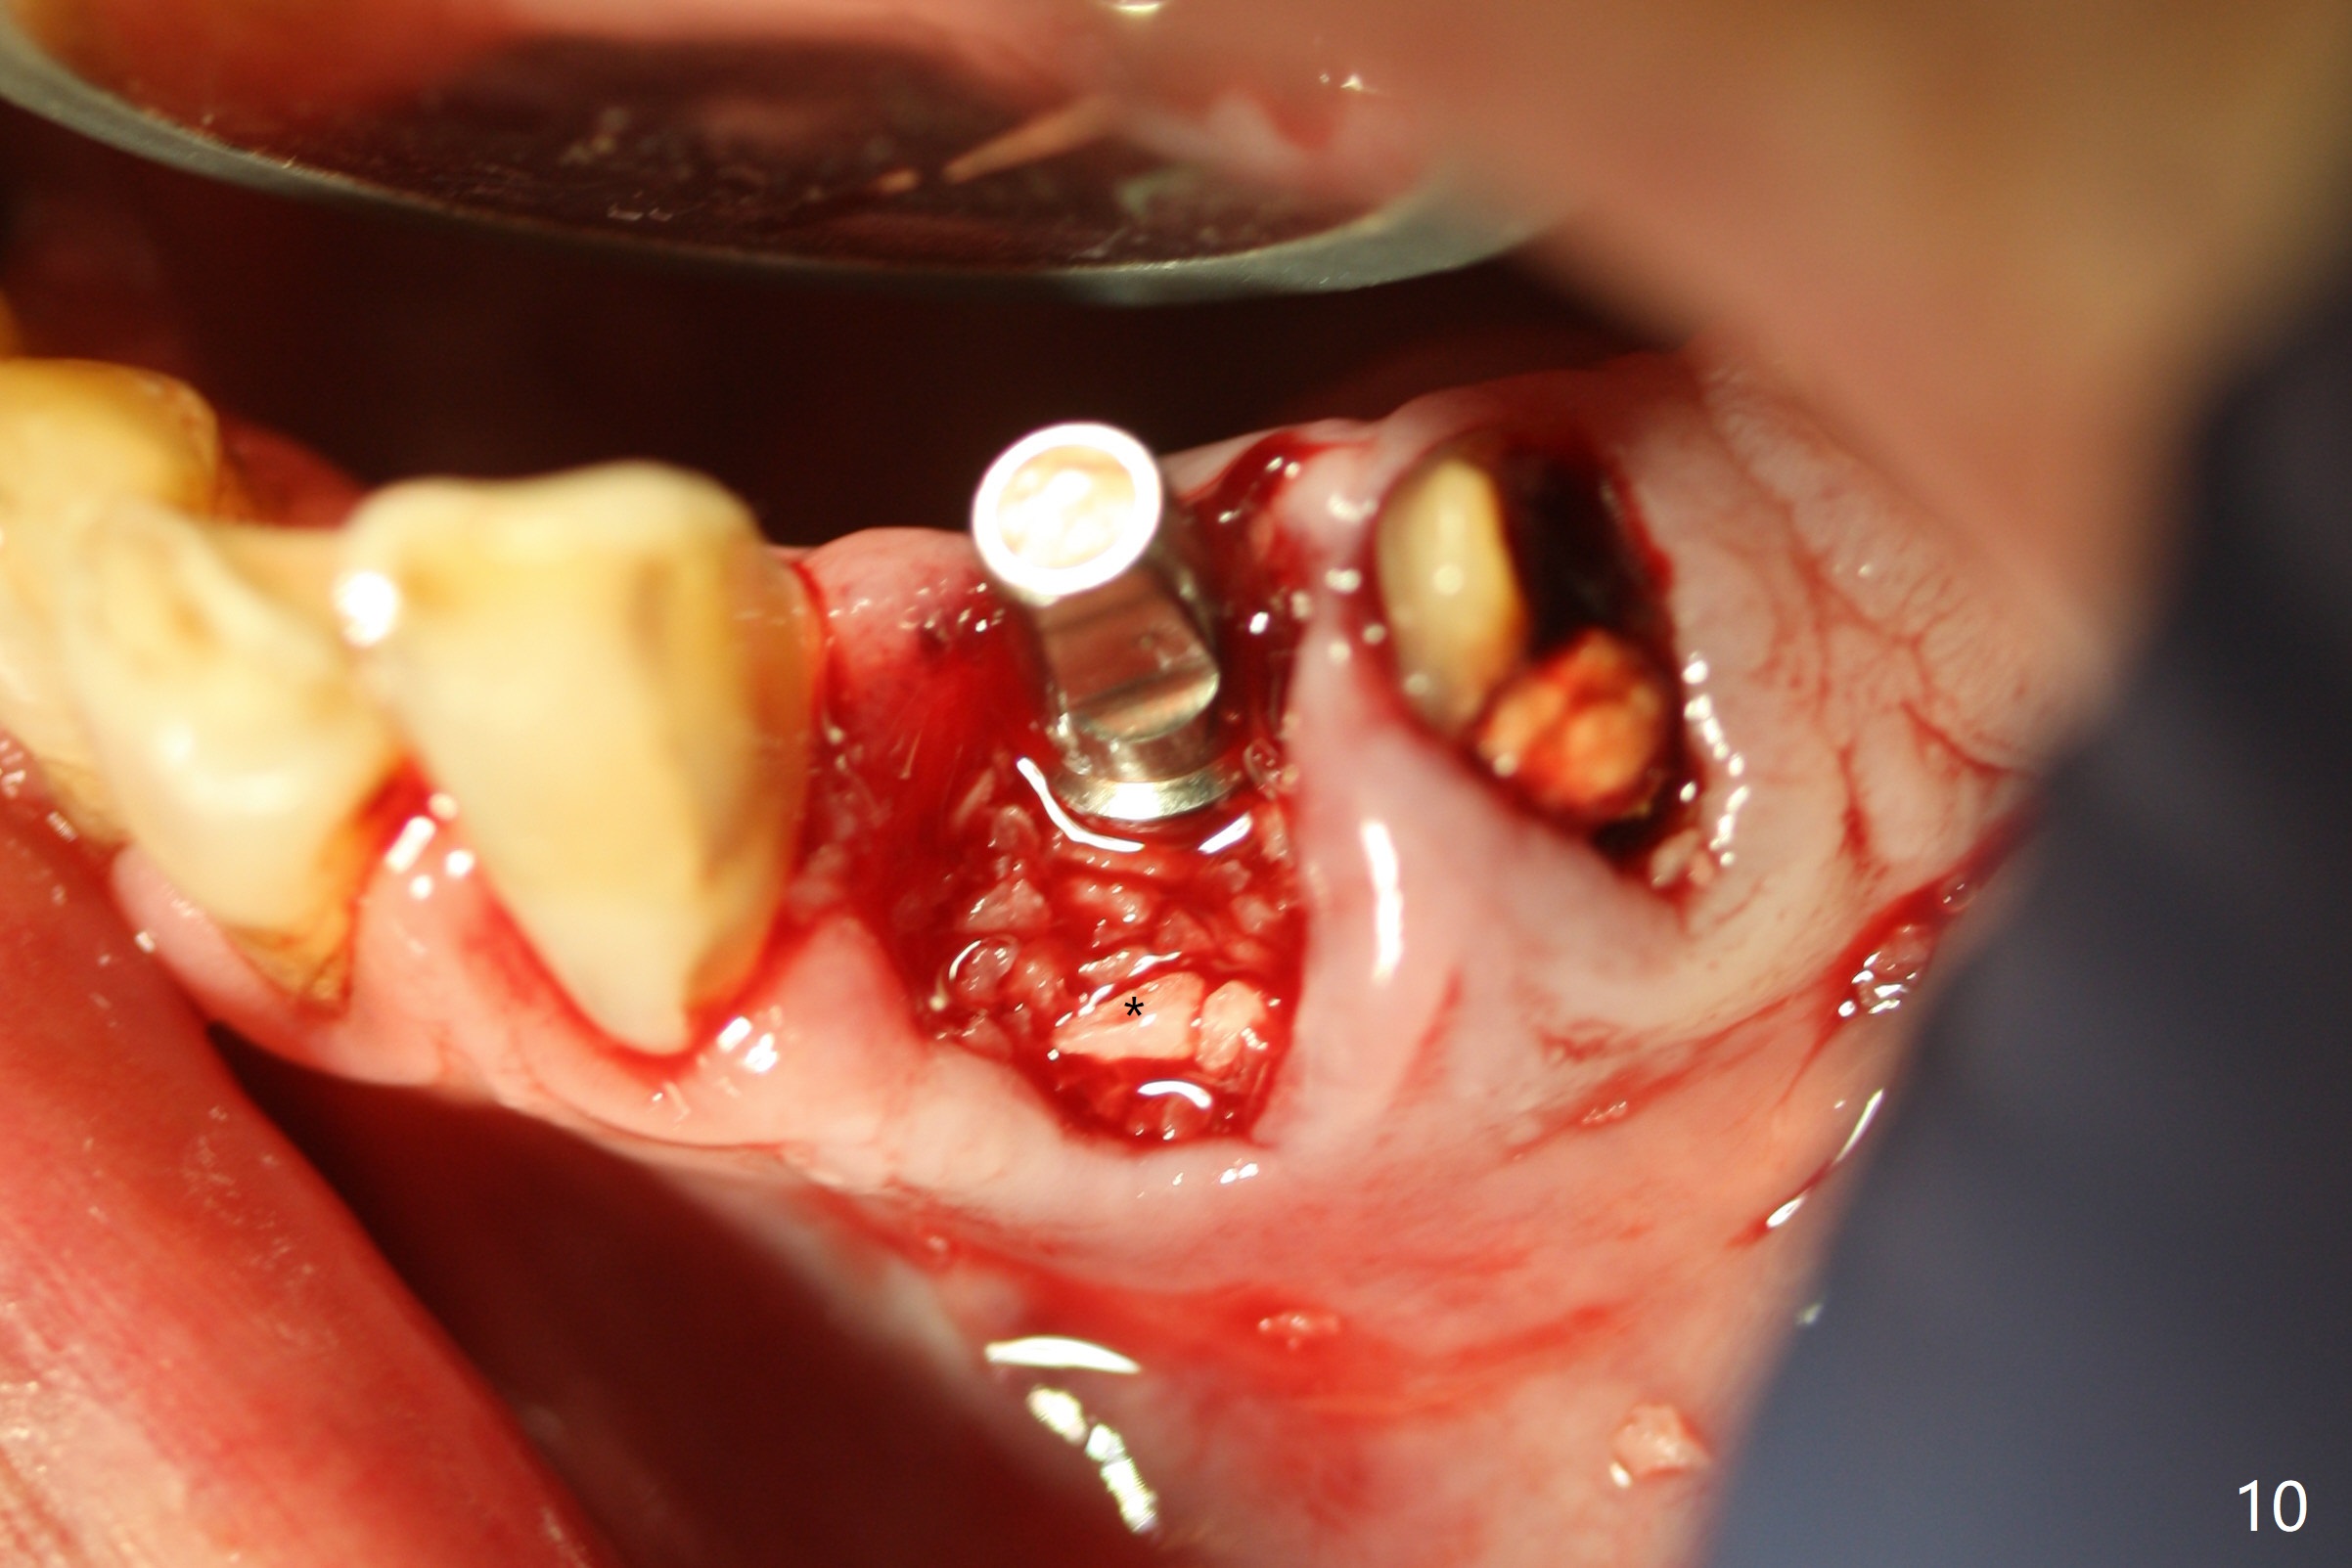

After removal of the split residual roots at #22 (Fig.1), the buccal wall is found to be defective, while the coronal portion of the lingual one (Fig.2 L) is confirmed to be more buccal than the apical portion. A vertical slot is made in the coronal portion of the lingual plate (Fig.3 *) in order to establish osteotomy lingual (Fig.4 O). The depth of the osteotomy in the apical native bone is 4.8 mm (Fig.5 CT coronal section). After the final drill (3 mm) is removed, a 3.8x16 mm implant is placed lingually for secure 2-pointed fixation (Fig.6,7, coronally: mesiolinguodistal; apically: in the native bone (Fig.9)). The essence of the lingual placement is the presence of a large buccal gap for Osteogen plug (Fig.8 yellow) and allograft (Fig.8 red, 9,10 (*)) for potential regeneration of the buccal plate. With bone graft and the overlying provisional (Fig.11 P), the buccal plate seems to have been established (*) 1 week postop. There is no obvious implant thread exposure 8 months postop (Fig.12). But the buccal plate is atrophic when the crown is cemented (~10 months postop, Fig.13).